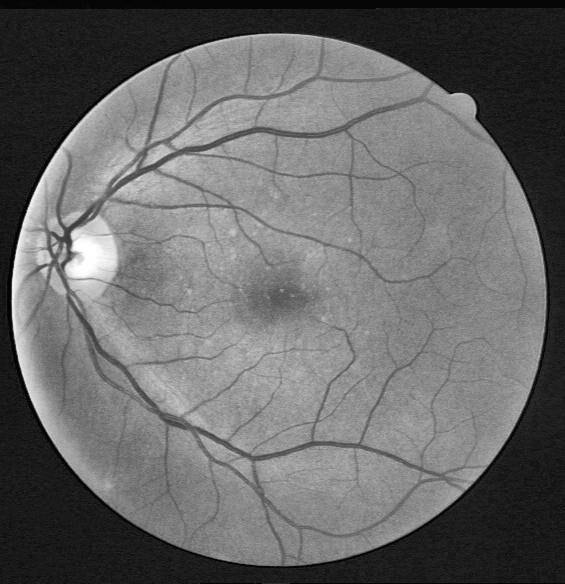

Datasets and Experimental Setup

The Digital Retinal Images for Vessel Extraction (DRIVE) [51] dataset is used for retinal segmentation. This dataset was collected in a study conducted in the Netherlands. 400400400400 individuals were recorded, where ages ranged between 2590259025-9025 - 90. This dataset consists of randomly selected 40404040 samples from the studied population. Retinal images for analysis were taken with a 3CCD camera that captured spherical areas from the center with a radius of 540540540540 pixels. Most samples (N=33)𝑁33(N=33)( italic_N = 33 ) are medically normal, while there are signs of diabetic retinopathy in 7777 samples. These 40404040 labeled color eye fundus images are equally distributed into train and test subcategories. For the training dataset, manual segmentation of each retinal fundus image’s retinal blood vascular tree is available. At the same time, two expert segmentation ground truths are available for the test dataset. It is a usual practice to set one of them as the gold standard, whereas the second is used as a benchmark.

Structured Analysis of the Retina (STARE) [52] is fundus images database that contains 20202020 retinal fundus images. The images are captured by a TopCon TRV-50 fundus camera. Among these images, 10101010 images are pathology-free, while the remaining 10101010 possess pathological abnormalities, which severely damage the anatomical structure of the eye. These abnormalities overlap blood vessels or sometimes make them completely complicated for analysis. This situation makes segmentation a much more complicated challenge to evaluate the performance in a more robust way. Like DRIVE, this dataset provides two sample sets of ground truth segmentation masks. The experiments in this paper were performed using Python. In particular, the Keras API with TensorFlow backend is used to construct the deep learning model. The proposed model is trained for 80808080 epochs. All the experiments have been conducted on the Google Colab platform, which provides free shared cloud services and supports GPU-Tesla K80,2496𝐾802496K80,2496italic_K 80 , 2496 CUDA cores, and 25252525 GB GDDR5 VRAM.

Results for DRIVE Test Images: Quantitative results of BLCB-CNN for all DRIVE images are computed, which shows that the proposed method achieves an average accuracy of 96.22. The average sensitivity/specificity value of 81.57/97.65 also indicates the model’s ability to accurately segment vessel pixels (including thin vessels). The AUC results are also consistent with the accuracy obtained for all the images. Figure 7 demonstrates the visual outcomes for two sample DRIVE images. It can be observed that the proposed method segmented both thin and thick vessels much closer to ground truth binary masks. This is further evident from the focused rectangular areas of the output/ground-truth images.

Cross Validation

Cross-validation is used to assess the performance of the proposed model on ten images from the STARE dataset. STARE images are more challenging due to the inherent lower quality and poor contrast of these images. However, the proposed model achieves reasonable performance on the STARE dataset images. Typically, training is conducted on STARE images using leave-one-out validation to test the model’s validity. Very few works have provided cross-validation to evaluate the stability of the learned model on the STARE dataset. The average values 88.06/96.31 for Se/Sp are quite promising and demonstrate the significant performance of the proposed model. The average AUC value is 97.57% that reflects the generalization of the proposed model on a completely unseen STARE dataset to demonstrate its generalization capability. Therefore, we, believe that our proposed methodology can be reliably applied for automatic retinal vessel segmentation of the clinical applications, such as a computer-aided diagnosis pipeline or automated vascular quantification or localization. Figure 8 depicts the visual outcomes for 2 sample images from the STARE dataset. As evident from a visual comparison of ground truth and output segmentation masks, thick vessels are detected quite accurately, especially near the fovea region. Similarly, thin vessel pixels at the branches are also segmented with reasonable visual match.